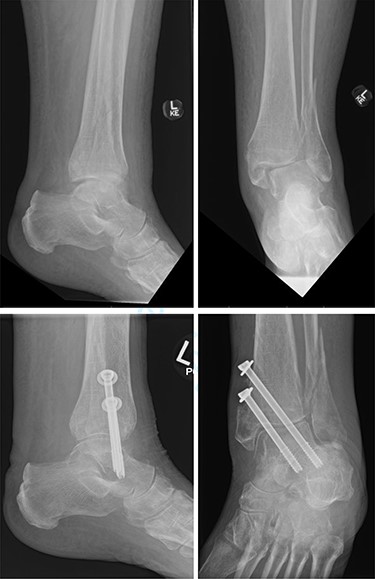

Overall, four out of six patients (66.7%) had satisfactory post-op radiographs with no evidence of talar shift, non/mal-union, widening of the syndesmosis or screw loosening (Figs 1 and 2).

Top—Fracture dislocated bimalleolar ankle fracture. Bottom—6 weeks post-operatively showing maintained tibiotalar alignment.